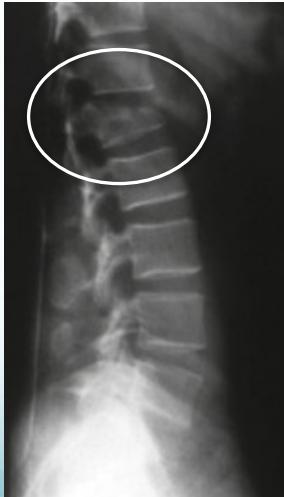

Wedge Compression

- Common in osteoporotic spine

- Mild trauma to old lady

- Usually stable

- Causes ↑kyphosis

Wedge Compression L-Spine

The Commonest Vertebral Injury

- Minor trauma in osteoporotic people

Stable Compression (posterior elements intact)

- Anterior vertebral body height reduced by < 50%

Unstable Compression (posterior elements injured)

- Anterior vertebral body height reduced by > 50%